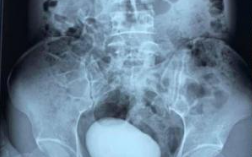

Једна снимак са скенера из вијетнамске болнице запањио је читав свет.

Фото: Принтсцреен / Тwиттер / заиролхамисам

Једна Вијетнамка дошла је у Хитну жалећи се на јак бол у пределу стомака, али и испод њега.

Како није могла више да трпи болове, медицински радници су је послали на скенер који је показао огромну, округлу масу у мокраћном каналу. То је био камен дуг десет центиметара и тежак 400 грама!

Фотографије камена од 400 грама обишле су друштвене мреже у Азији, а многи се питају како је уопште жена могла да подноси такву бол.